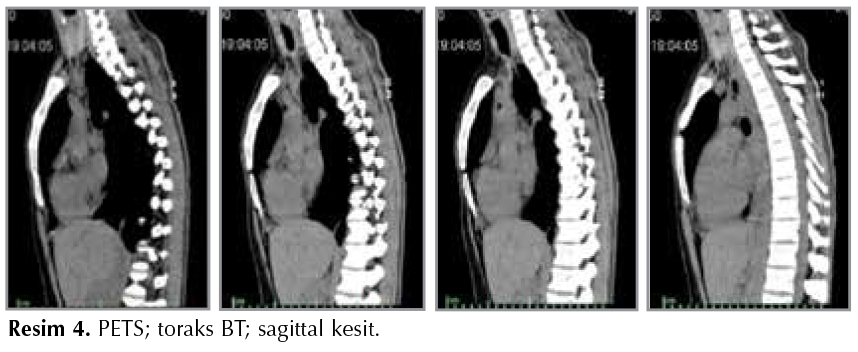

Diğer bir g?r?nt?leme y?ntemi bilgisayarlı tomografidir (Resim 3,4). ?zellikle iki boyutlu kesitler elde edildiğinde trakeayı doğru bir şekilde g?r?nt?lemeye yarayan, noninvaziv bir y?ntemdir. Darlığın lokalizasyonunu, tipini, boyutlarını, damarsal yapılarla ilişkisini, kıkırdak yapının b?t?nl?ğ?n? ve distal hava yollarını ?zellikle de girişimsel işlemler ?ncesi daha iyi değerlendirmeyi sağlar. Sonradan teknik olarak elde edilebilecek "sanal bronkoskopik g?r?nt?ler" de değerlendirmeye katkı sağlayabilir (17).

Resim 3

Resim 4